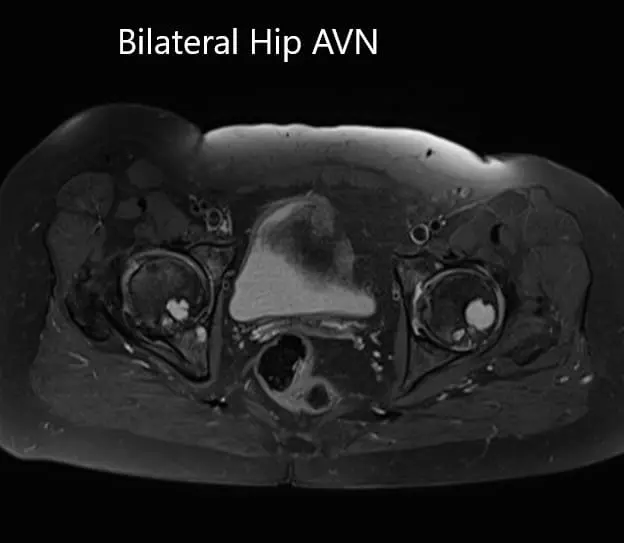

MRI was obtained which showed:

Right Hip Joint: There is a loss of sphericity of right femoral head, involving more than 2/3 of the circumference. In the superior part of the right femoral head, a focal lesion is visualized which is bounded by a serpiginous T1 hypointense margin. The lesion is hypointense on both T1 & T2WI relative to the marrow (Mitchell class – D).

No subchondral fracture is detected. A minimal amount of fluid is seen in the joint cavity. The femoral neck and acetabulum display normal signal intensity. Muscles in view display normal signal intensity.

Left hip joint: Displays similar although less severe changes. The sphericity of the left femoral head is maintained. There is more than 2/3 circumferential involvement of the left femoral head. No subchondral fracture is seen. No joint effusion is seen.

Axial sections of T1WI and T2WI of the pelvis MRI.